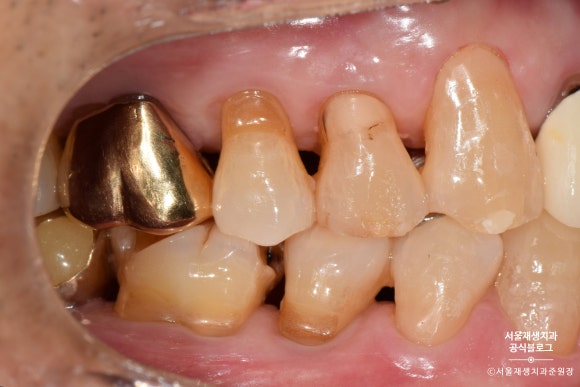

전방치아는 레진으로, 후방치아는 GI로 치료한 사례

여러 치아에 동시에 발생한 치경부마모증을 치료한 사례입니다.

환자분과 거울을 보며 상의한 결과,

잘 보이는 전방 치아는 레진으로,

잘 보이지 않는 후방 치아는 글라스아이오노머로 치료하기로 결정했습니다.

치아의 목 부분, 다시 말해 잇몸과의 경계 부위에

짙은 오렌지색의 띠가 보이시나요?

치아의 겉면은 하얗고 투명한 법랑질인데 반해,

치아의 속살은 노랗고 불투명한 상아질입니다.

법랑질이 모두 마모되어 상아질이 노출되었고,

법랑질에 비해 무른 상아질이 안으로 파고들듯이 마모되고 있는 상태였습니다.

제법 진행이 많이 된 치아를 선별하여

총 4개의 치아를 치료하기로 했습니다.

노란색으로 표시된 치아들은 상대적으로 전방에 위치하여 레진으로 치료하기로 했습니다.

연두색으로 표시된 치아들은 상대적으로 후방에 위치하여, 심미성이 조금 떨어지더라도 비용이 저렴한 글라스아이오노머로 치료하기로 했습니다.